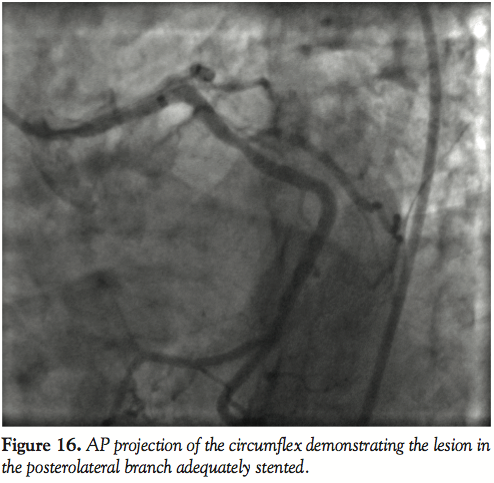

Case 5. A distal lesion in a small posterolateral vessel was successfully treated after very deep engagement of the GuideLiner catheter (Figures 14–16). In the past, this lesion would either be treated medically or with balloon angioplasty, but with the availability of drug-eluting stents in smaller diameters (2.25 mm) and low late loss of 0.1 mm, these patients can be offered relief of their angina as was demonstrated in this case. Caution needs to be exercised with such maneuvers with the catheter.